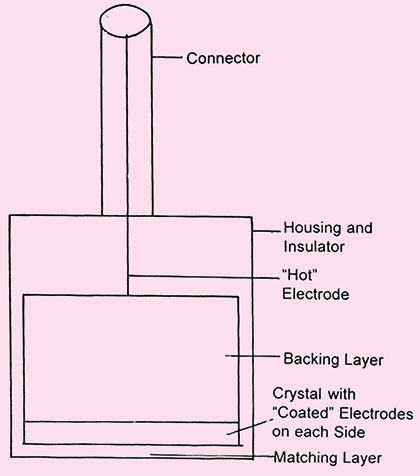

The ultrasound waves are generated by mechanical oscillation known as transducer (Fig. 1.1).

In this crystal is excited by high frequency electrical pulses which causes mechanical oscilation and that produces ultrasound waves. Hence electrical energy is converted into mechanical energy.2

As these ultrasound waves passes through the medium a portion of us energy is reflected back towards the transducer and received by transducer in the form of an echo. These returning echoes in reverse converted by the same piezoelectric crystal (conventional B-mode ultrasonography) which converts echos into electric pulses that are used to generate sonographic image. Therefore transducers are both transmitter (converts electrical energy into ultrasound waves) and receiver (converts reflected portion of ultrasound waves into electrical signals) of ultrasound.